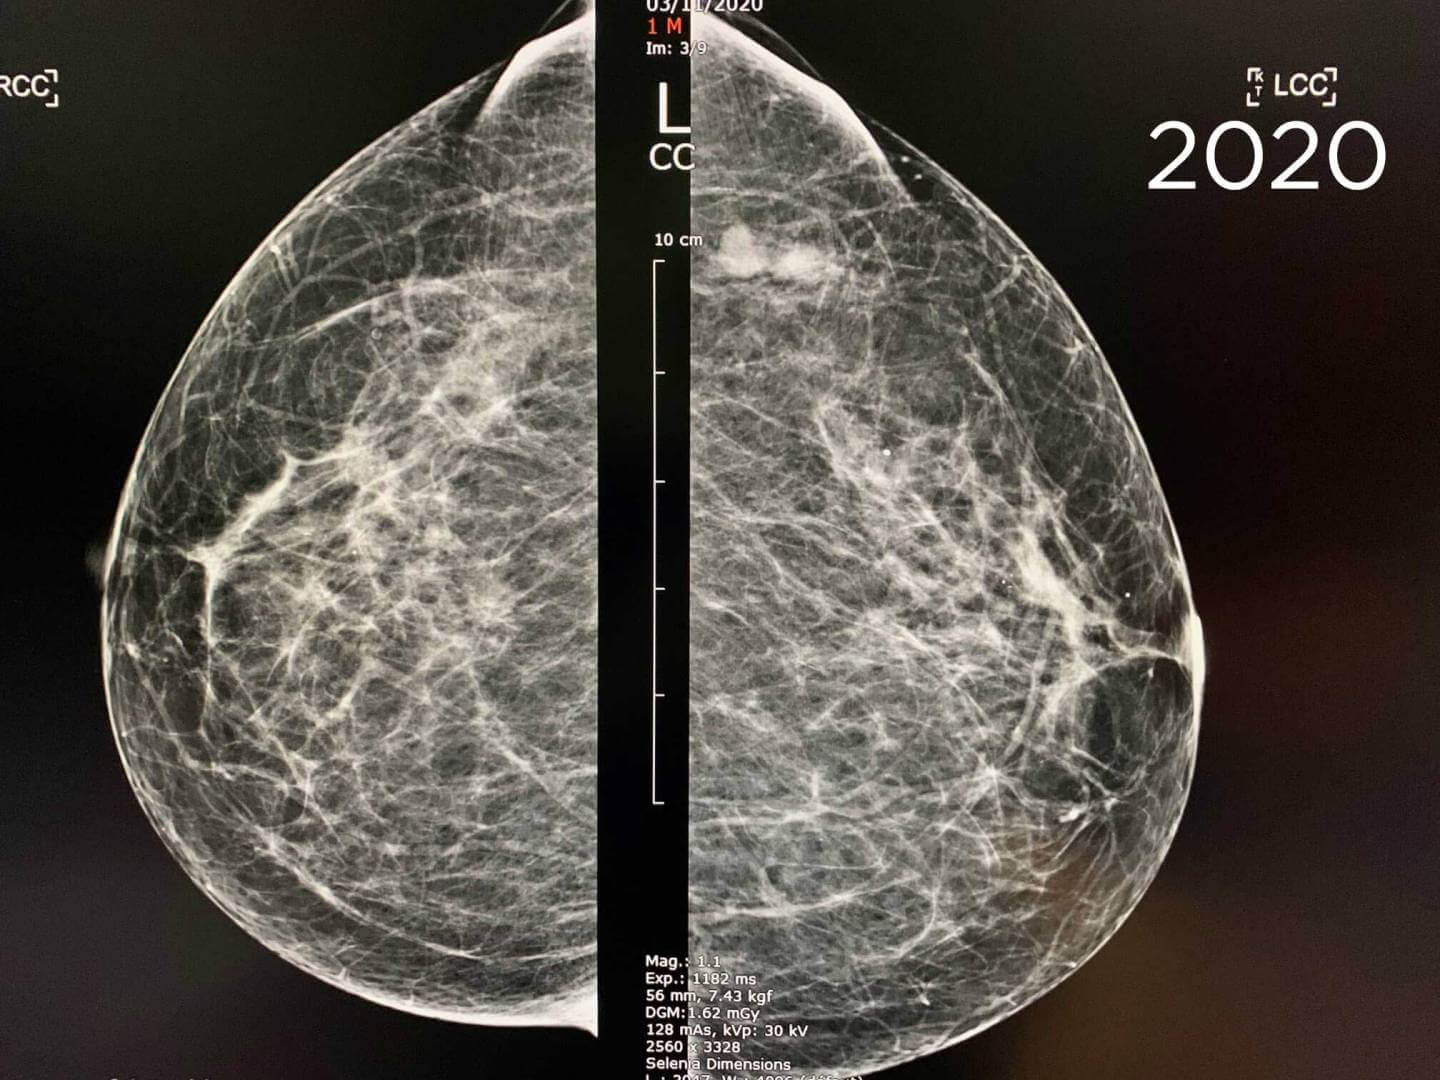

Cas de la semaine (semaine 35, 2021)

Mammographie de dépistage. Patiente de 73 ans

L’examen est comparé à l’examen de 2018, il existe 2 opacités accolées du prolongement axillaire gauche présente sur l’examen de 2018 évoquant des ganglions intramammaires.

Pourtant, Mammoscreen™ pointe ces lésions et met un drapeau rouge.

La mammographie est tout de même considérée bénigne et envoyée en seconde lecture.

Le second lecteur demande un complément échographique et un cliché localisé devant l’augmentation des lésions entre 2018 et 2020.